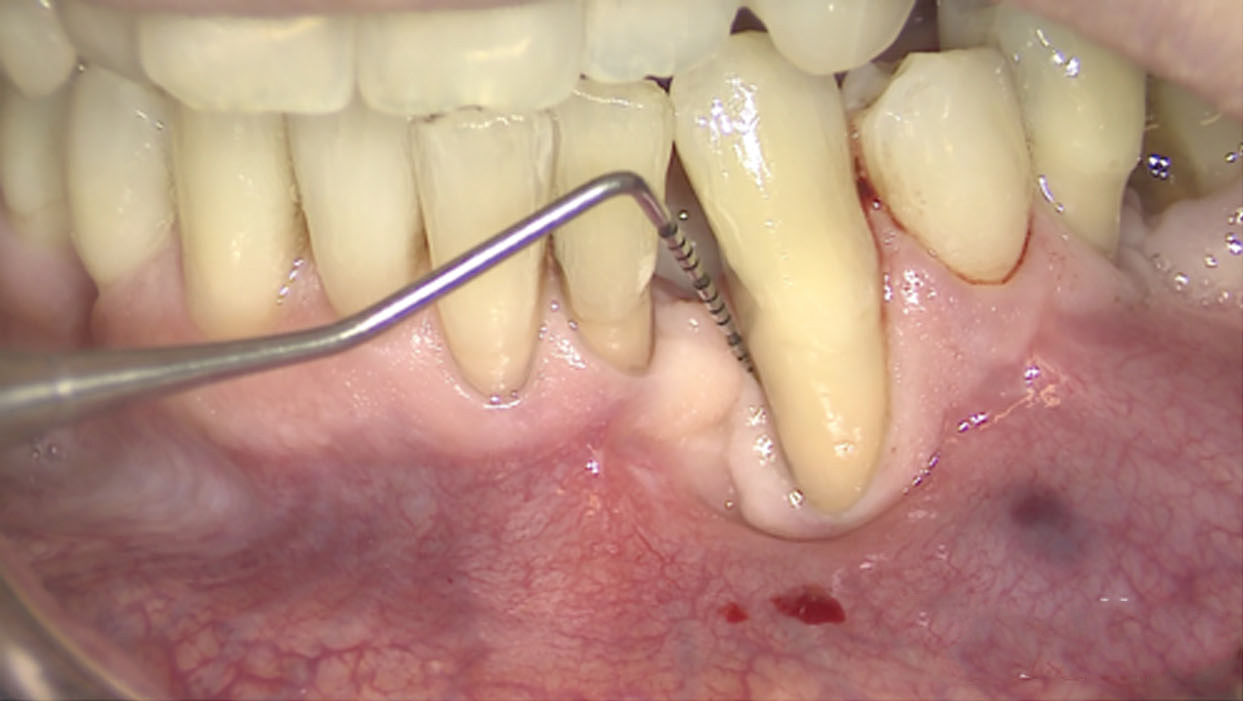

Fig 13. The scaffold was placed in the defect, where it remained for approximately 1 year. Fig 13: baseline; Fig 14: defect; Fig 15: scaffold matrix; Fig 16: scaffold placement; Fig 17: wound closure; Fig 18 through Fig 20: 2-month, 6-month, and 1-year postoperative, respectively. (Images reprinted with permission from Rasperini G, Pilipchuk SP, Flanagan CL, et al. J Dent Res. 2015;94[9 suppl]:153S-157S.)

Figure 13

Fig 14. The scaffold was placed in the defect, where it remained for approximately 1 year. Fig 13: baseline; Fig 14: defect; Fig 15: scaffold matrix; Fig 16: scaffold placement; Fig 17: wound closure; Fig 18 through Fig 20: 2-month, 6-month, and 1-year postoperative, respectively. (Images reprinted with permission from Rasperini G, Pilipchuk SP, Flanagan CL, et al. J Dent Res. 2015;94[9 suppl]:153S-157S.)

Figure 14